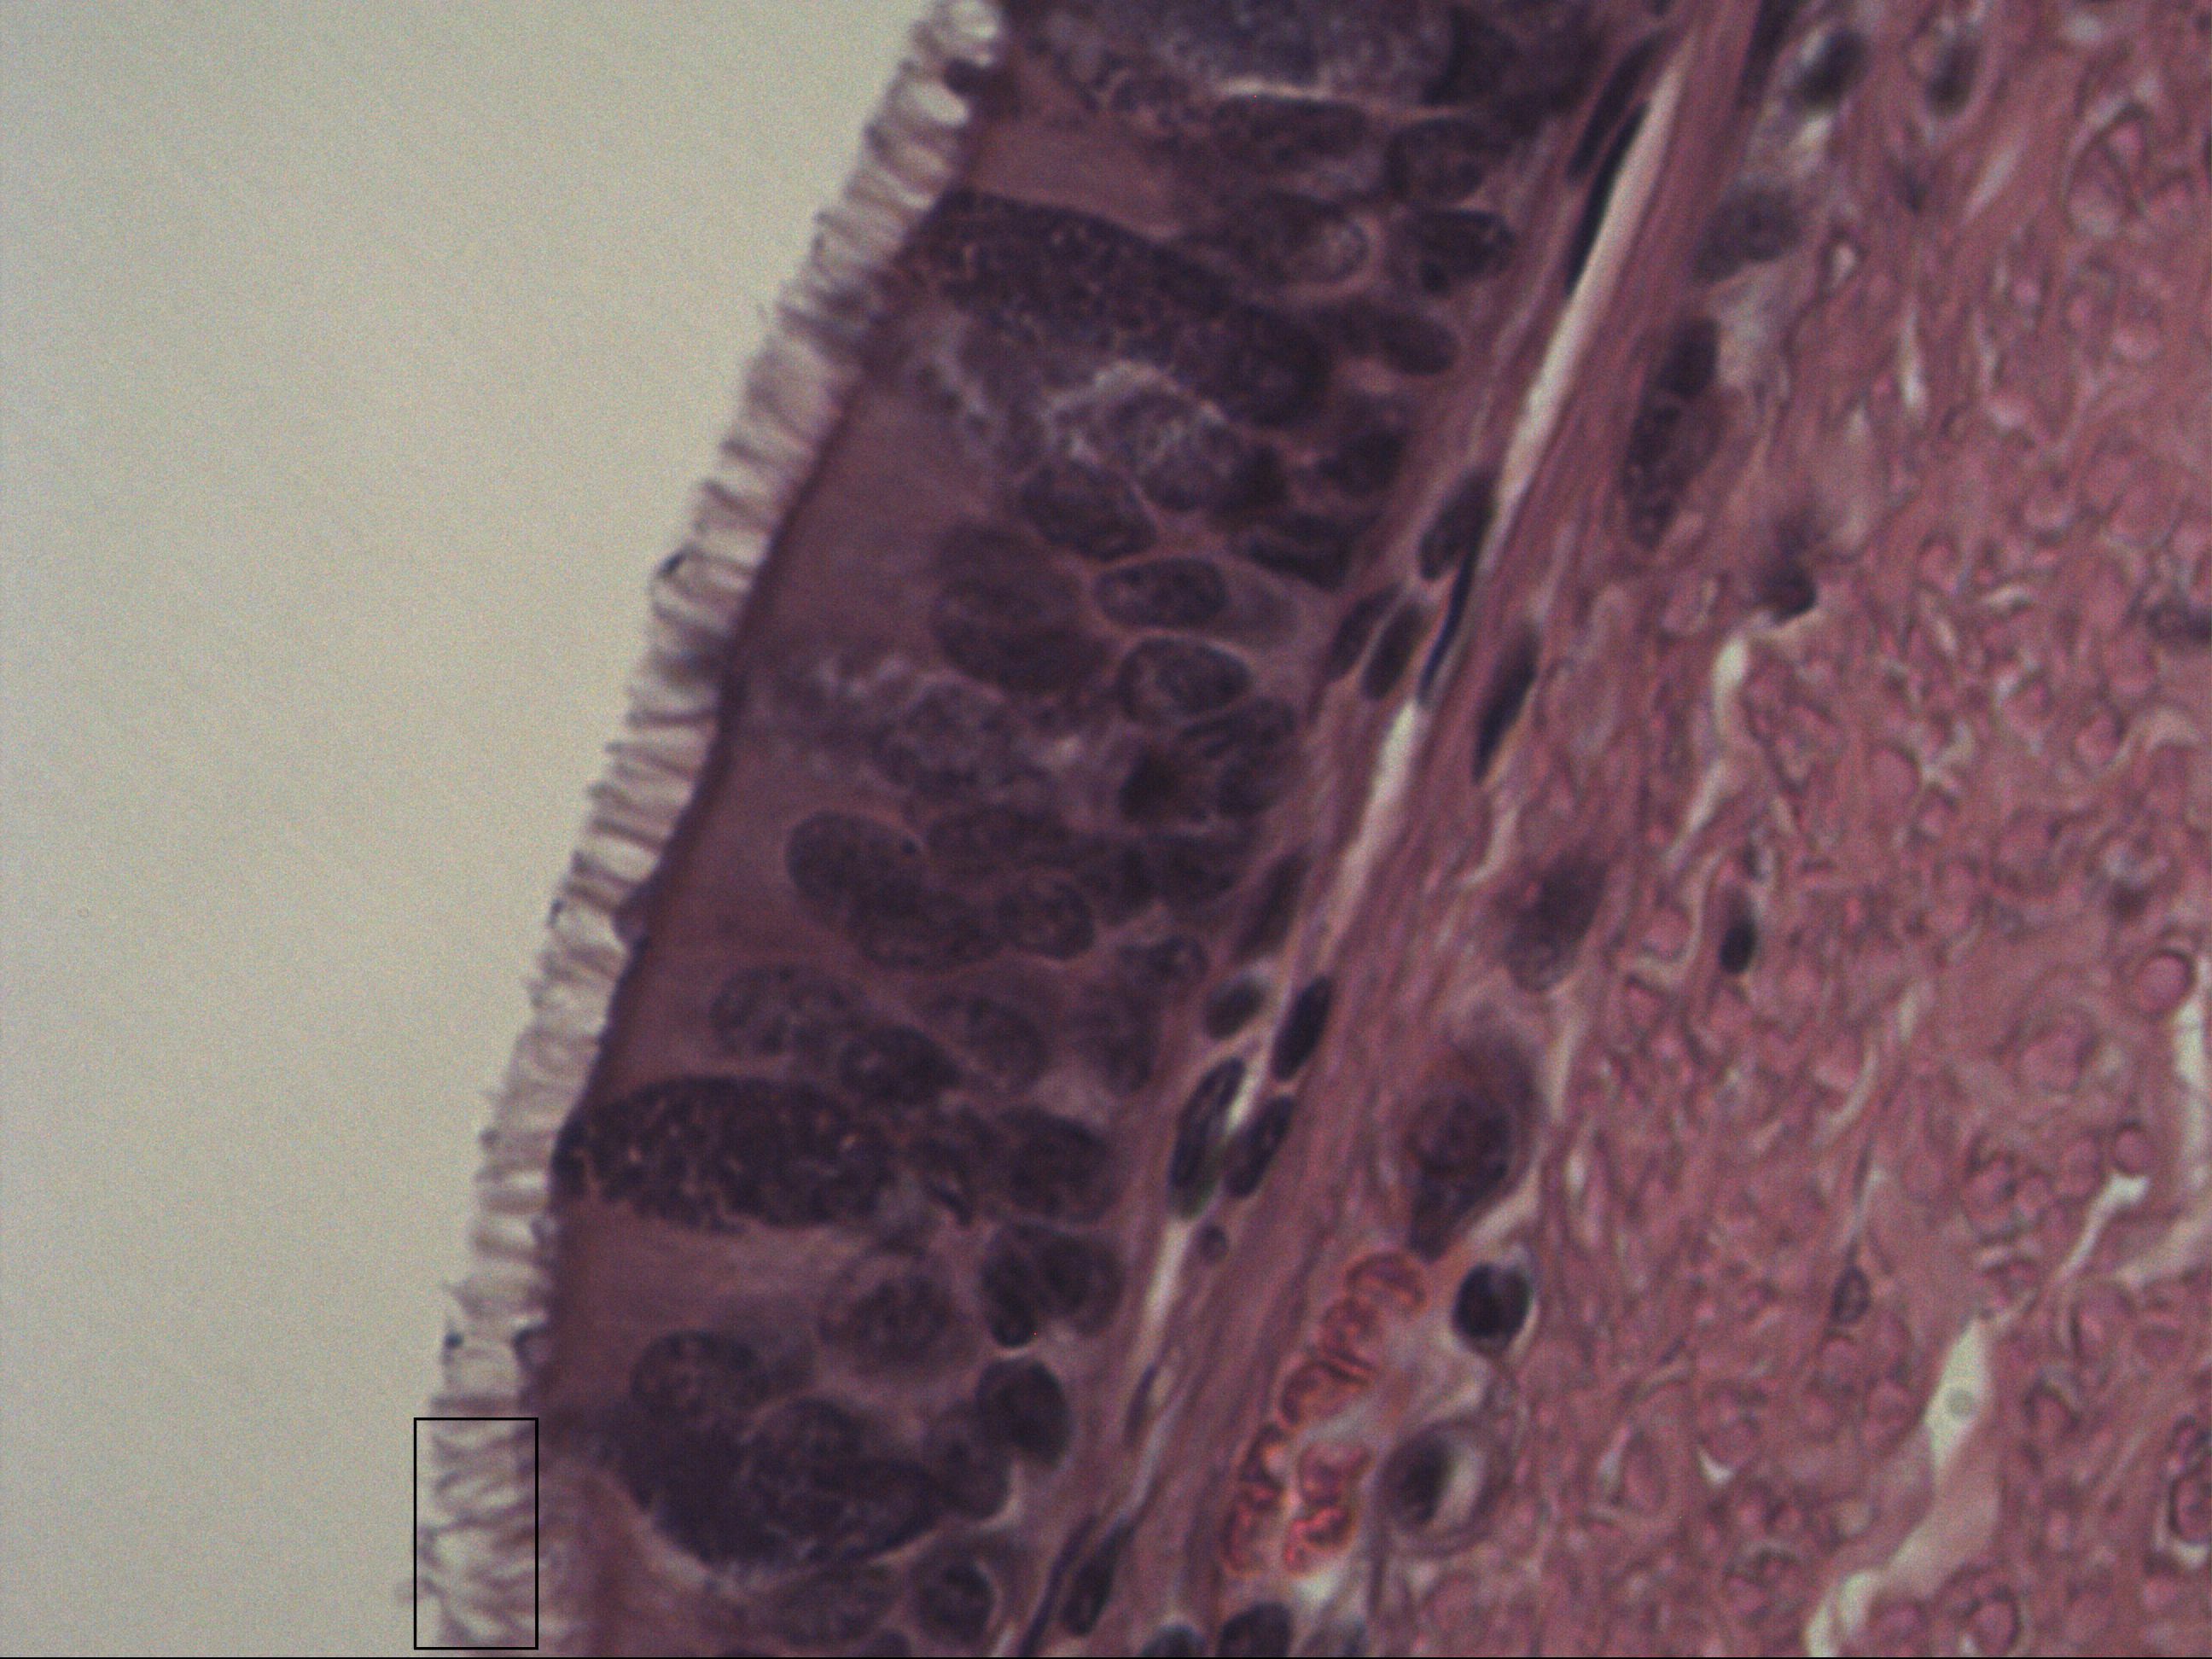

Mehrreihiges hochprismatisches Epithel mit Kinozilien

Trachea [HE]

Mehrreihiges hochprismatisches Flimmerepithel mit Kinozilien. Man erkennt Basalzellen und etwas höher gelegene Zellen am Zellkern. Das Flimmerepithel besitzt Kinozilien. Das Epithel kann sich bei Rauchern in ein Plattenepithel umwandeln (Metaplasie).